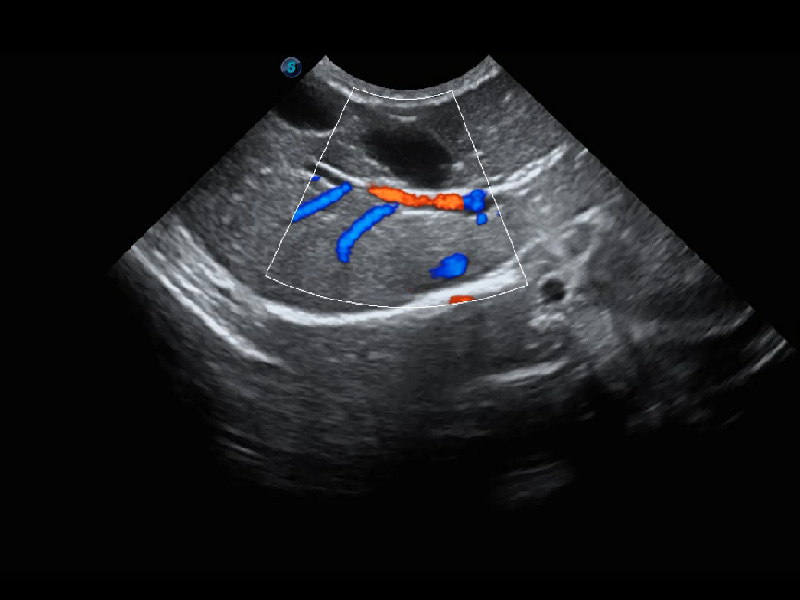

ProPet 60 作为一款高端台式动物超声设备,为动物医生的日常诊断提供了一系列贴合动物临床需求、解决临床实际问题的高级成像功能。凭借全系列高清探头,满足医生对腹部、心脏、生殖、浅表、肌骨等成像的所有需求,切实帮助您提升检查效率,提高诊断信心。

动物是人类最亲密的朋友和最值得信赖的伙伴。百老汇电子游戏官网也一直致力于探索动物专用的超声影像解决方案。 全新推出的ProPet系列,是百老汇电子游戏官网在动物超声影像智能化、专业化、精准化的一次跨越式革新。动物不能用言语来表述自己的不适,通过超声影像,ProPet系列搭建了动物医生与不同物种沟通的“桥梁”,为动物医生注入了“治愈之力”。